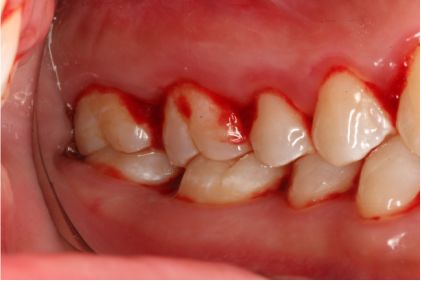

超声洁刮治术即刻

采用PT5牙周治疗仪进行全口超声龈上洁治术、超声龈下刮治术。术后5周复查可见牙龈炎症明显减轻,仍有轻度炎症,复查发现患者口腔卫生维护欠佳,再次进行口腔卫生宣教。